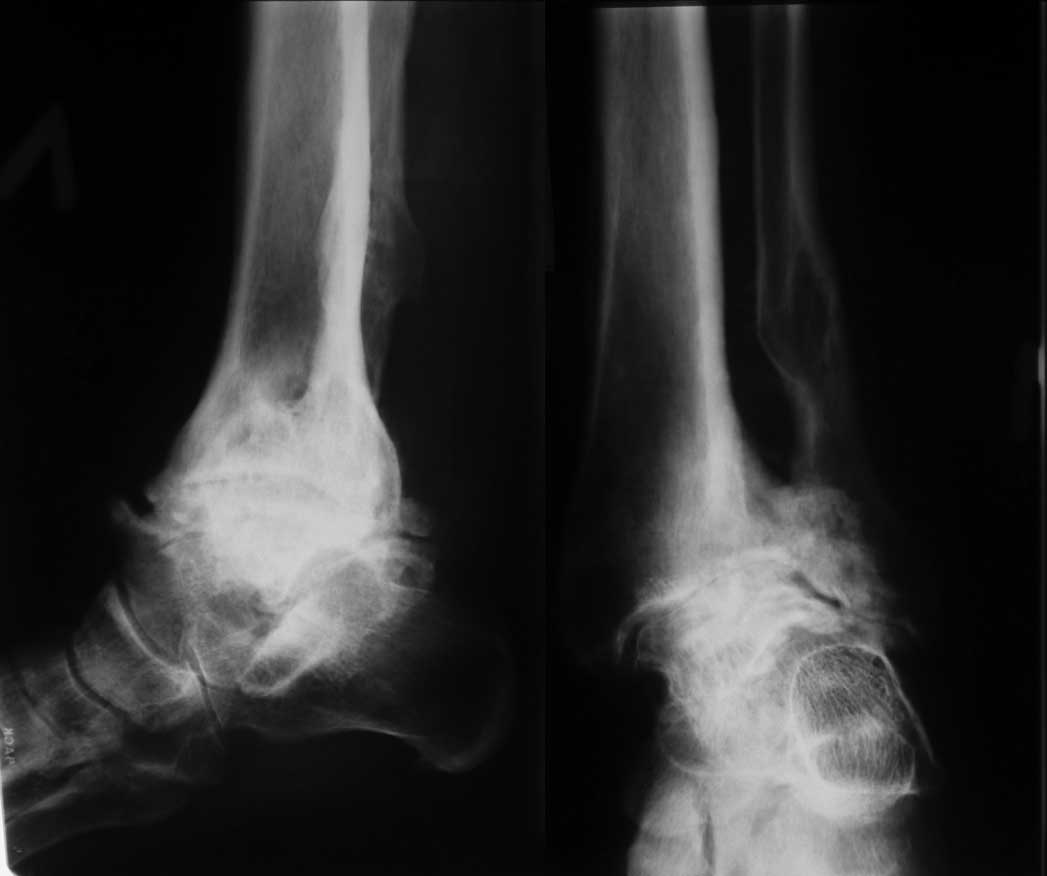

Уважаемые коллеги. Пациентка 1948 г.р., беспокоят боли в области левого голеностопа, прогрессирующая деформация(варусная) и неустойчивость сустава.Травму отрицает. Болеет более 5-ти лет. Согласна на операцию. Вопрос об артродезе г/ст сразу не вызывал сомнений. Но, если это артропатия, то насколько велик риск несращения? Помогите определиться с диагнозом и сответственно с тактикой. Невролог патологии не находит. Во вложенных файлах рентгенограммы за 2007 и 2012 гг.? фото и КТ свежая.

Вопрос, как я писал, в том что это такое- артропатия или артроз. Мне, например, не доводилось видеть нетравматический остеоартроз голеностопного сустава с прогрессирющей варусной деформацией и выраженной кистозной перестройкой. А несращение после резекции голеностопа у больного артропатией видел. В том случае коллеги дважды фиксировали блокирующим гвоздем и пациент ходил, пока держал металл и в настоящий момент планируется 3 синтез.

It looks like an end-stage probably either of neuropathic joint or Tibialis Posterior insufficiency.

У пациентки резко выраженная вальгусная деформация стопы. При попытке выполнения артродеза без коррекции оси конечности вероятность несостоятельности артродеза и сохранения болей крайне велика. Артроз имеет односторонний характер и связан, с большой степенью вероятности, с нарушением оси конечности. При восстановлении правильной оси такой сустав сможет послужить еще не один год. В плане дообследования обязательны снимки в переднезадней проекции под нагрузкой с захватом бугра пяточной кости, которые помогут лучше оценить осевые взаимоотношения голени и стопы. Исправить эти взаимоотношения можно, как путем медиализирующей остеотомии пяточной кости, так и путем остеотомии большеберцовой кости. Сохраняющая голеностопный сустав хирургия сейчас на подъеме, ей посвящаются симпозиумы, статьи. Она служит, как для сохранения сустава, так и для подготовки последующих успешных операций артродезирования или протезирования.

Да, лучше бы сразу фото двух стоп выложили. А то уж больно первая фотография на вальгусную деформацию похожа. И все-таки ось голени и стопы должна быть восстановлена тем или иным способом. Без этого вероятность несостоятельности артродеза очень велика.